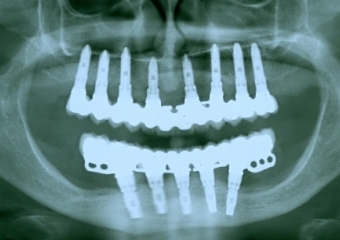

Raio X final

Raio X de 24 meses de controle